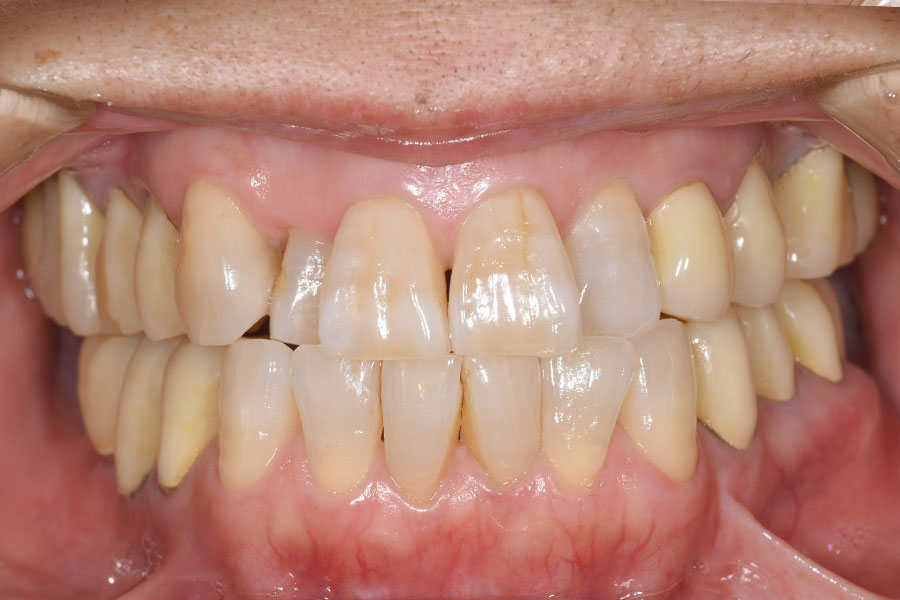

Before -正面-

After -正面-

| 施術内容 | 金属アレルギー予防を目的に、金属フリーの自費補綴へ変更。適合性・清掃性・審美性の向上が得られています。 |

|---|---|

| 治療期間 | 約4ヶ月 |

| 費用 | ハイブリットクラウン ハイブリットインレー 693,000円 |

| リスク・副作用 | 治療にともない、歯の破折や歯質の削合、場合によっては抜歯が必要となることがあります。また、金属や補綴物を除去する際に、完全に除去できない場合もあります。 |